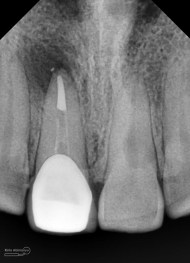

Foto radiografis setelah pengisian

Foto radiografis setalah pemasangan pasak dan pembuatan core

dan ini hasil ronsen final…

Foto radiografis akhir

Terlihat padat dan hermetis dari ujung sampai ke crown….